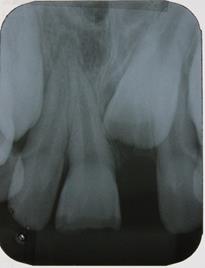

Na sessão seguinte, foi realizada restauração direta do incisivo central superior direito com RCMC Vittra APS Unique (FGM Dental Group, Joinville-SC, Brasil). Na oportunidade, considerando a extensão da fratura, para a restauração da face palatina foi utilizada matriz de silicone (Perfil, Coltene, Rio de Janeiro-RJ, Brasil). A sequência clínica restauradora abrangeu: 1) Anestesia infiltrativa, com mepivacaína 2% (vasoconstritor adrenalina 1:100.000), para remoção do CIV, com broca esférica #2 Jet carbide (Labordental, São Paulo- SP, Brasil), montada em baixa rotação; 2) Acabamento do esmalte no ângulo cavo superficial, com ponta diamantada #1190F (Kavo, Joinville-SC, Brasil); 3) Profilaxia dos dentes anterossuperiores com pasta de pedra-pomes e água, com auxílio de escova de Robson (Ultra-soft, American Burrs, Palhoça-SC, Brasil), montada em baixa rotação; 4) Isolamento absoluto modificado; 5) Condicionamento ácido do esmalte e da dentina com ácido fosfórico 37% (Biodinâmica, Ibiporã-PR, Brasil), durante 30 segundos em esmalte e 15 segundos em dentina; 6) Lavagem com jato de água para remoção do agente condicionador, durante 30 segundos; 7) Secagem do campo operatório com jato de ar e da dentina condicionada, com filtro de papel (Melitta, São Paulo-SP, Brasil); 8) Aplicação de duas camadas do sistema adesivo (SA) (Adper Single Bond 2, 3M ESPE, Sumaré-SP, Brasil), com auxílio de pincel microaplicador (Cavibrush regular, FGM, Joinville-SC, Brasil), de forma ativa, por 15 segundos; 9) Remoção do excesso de SA com auxílio de pincel microaplicador limpo e intervalo de tempo para evaporação do solvente; 10) Fotoativação do SA com aparelho Radii-Call-SDI (Southern Dental Industries, São Paulo- SP, Brasil), com potência de 1200 mw/cm2, por 20 segundos; 11) Posicionamento da matriz de silicone (Figura 3) para restauração da face palatina, a partir da inserção da RC Vittra APS Unique (FGM Dental Group, Joinville-SC, Brasil), e fotoativação com o aparelho à base de LED; 12) Por meio da técnica incremental, com auxílio de

espátula de inserção e pincel, foi realizada a restauração da área correspondente à dentina com RC Vittra APS Unique (FGM Dental Group, Joinville-SC, Brasil) com caracterização do volume e anatomia (sulcos de desenvolvimento) desse substrato (Figura 4). A RC também foi inserida sobre o ângulo cavo superficial para mascarar a linha de transição entre dente e área restaurada até completar toda face vestibular. Todos os incrementos de RC foram fotopolimerizados por 40 segundos; e 13) Acabamento imediato da